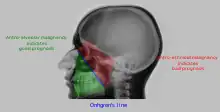

![]() Onhgren's line